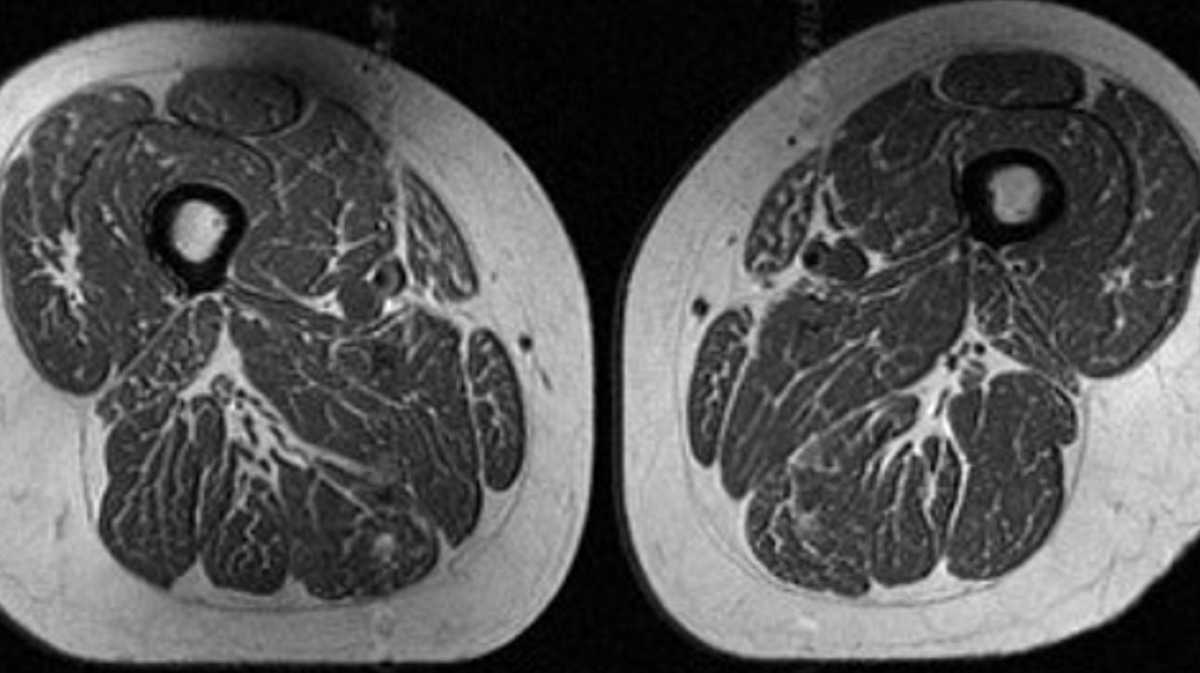

The image looks like a slice of highly marbled flesh, reminiscent of a high-end steak with abundant fine-grained streaks of fat. But that’s not dinner. It’s an MRI scan of the thigh of a 62-year-old woman who obtained 87% of her annual calories from ultraprocessed food.

A 61-year-old woman in the study also had fat marbling in her thigh muscles, but it was not as intense. About 29% of her annual diet consisted of ultraprocessed foods.

The 61-year-old woman with a diet consisting of 29.5% ultraprocessed food (A in image below) had a slightly higher BMI of 32.6 and a much lower activity score than the woman (B in image) with a BMI of 31.8 whose diet was 87.1% ultraprocessed. Yet the woman with the higher ultraprocessed score still had dramatically more fat marbling in her thighs.